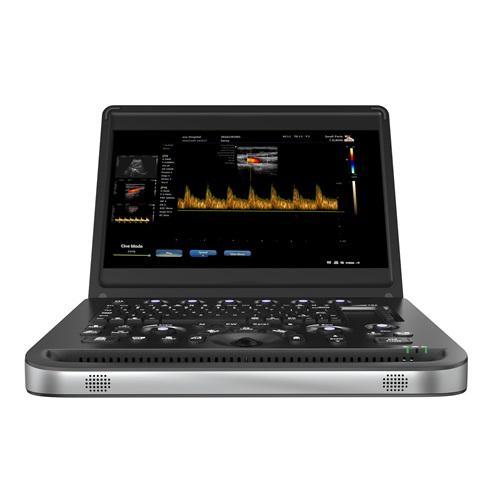

Advanced Color Doppler Ultrasound Techno

How to select color Doppler ultrasound in 2026? Hawmed system analysis with technical specifications, clinical applications, and procurement